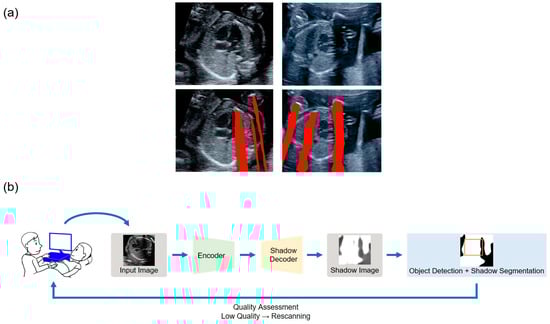

- Dozen, A.; Komatsu, M.; Sakai, A.; Komatsu, R.; Shozu, K.; Machino, H.; Yasutomi, S.; Arakaki, T.; Asada, K.; Kaneko, S. Image Segmentation of the Ventricular Septum in Fetal Cardiac Ultrasound Videos Based on Deep Learning Using Time-Series Information. Biomolecules 2020, 10, 1526. [Google Scholar] [CrossRef]

- Komatsu, M.; Sakai, A.; Komatsu, R.; Matsuoka, R.; Yasutomi, S.; Shozu, K.; Dozen, A.; Machino, H.; Hidaka, H.; Arakaki, T.; et al. Detection of Cardiac Structural Abnormalities in Fetal Ultrasound Videos Using Deep Learning. Appl. Sci. 2021, 11, 371. [Google Scholar] [CrossRef]